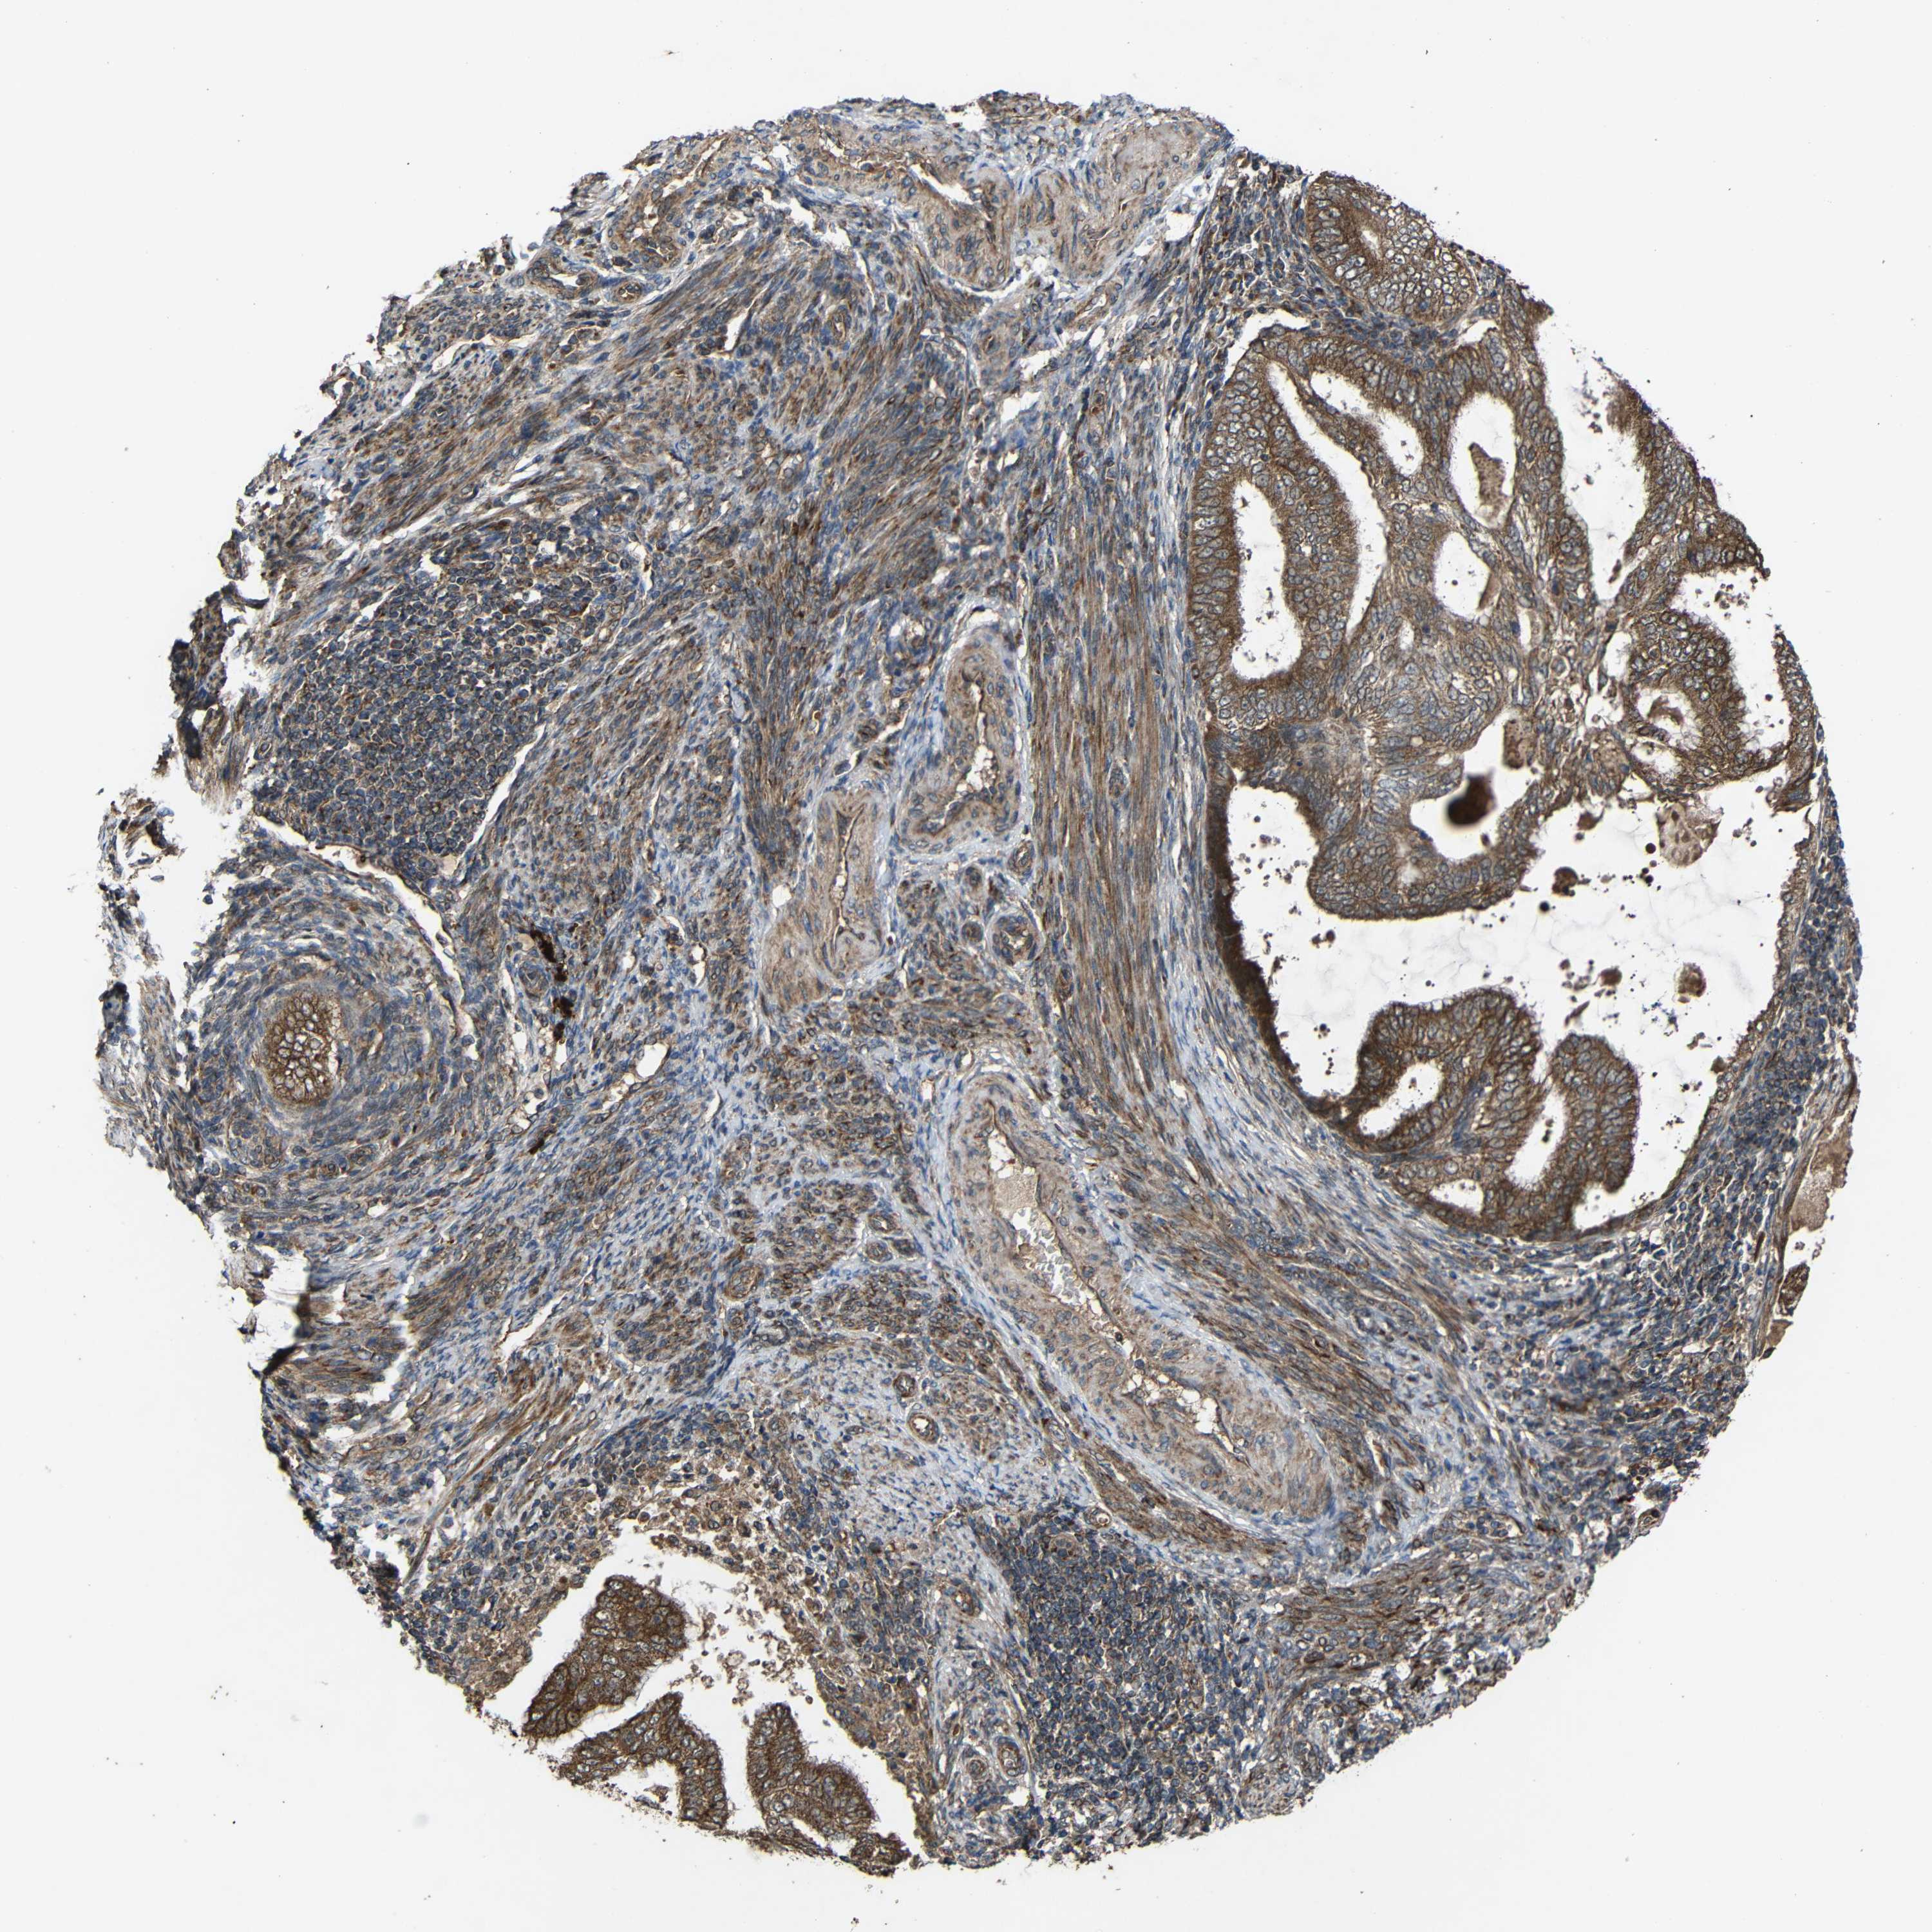

ENDOMETRIAL CANCER - Protein expressioni

A mouse-over function shows sample information and annotation data. Click on an image to view it in a full screen mode. Samples can be filtered based on level of antibody staining by selecting one or several of the following categories: high, medium, low and not detected. The assay and annotation is described here.

Note that samples used for immunohistochemistry by the Human Protein Atlas do not correspond to samples in the TCGA dataset.

Antibody stainingi

Antibody staining in the annotated cell types in the current human tissue is reported as not detected, low, medium, or high, based on conventional immunohistochemistry profiling in selected tissues. This score is based on the combination of the staining intensity and fraction of stained cells.

Each image is clickable and will lead to virtual microscopy that enables deeper exploration of all samples and also displays staining intensity scores, fraction scores and subcellular localization as well as patient and tissue information for each sample.

Antibody HPA011294

Antibody HPA012819

Staining

High

Medium

Low

Not detected

Intensity

Strong

Moderate

Weak

Negative

Quantity

>75%

75%-25%

<25%

None

Location

Nuclear

Cytoplasmic/membranous

Cytoplasmic/membranous,nuclear

Adenocarcinoma, NOS